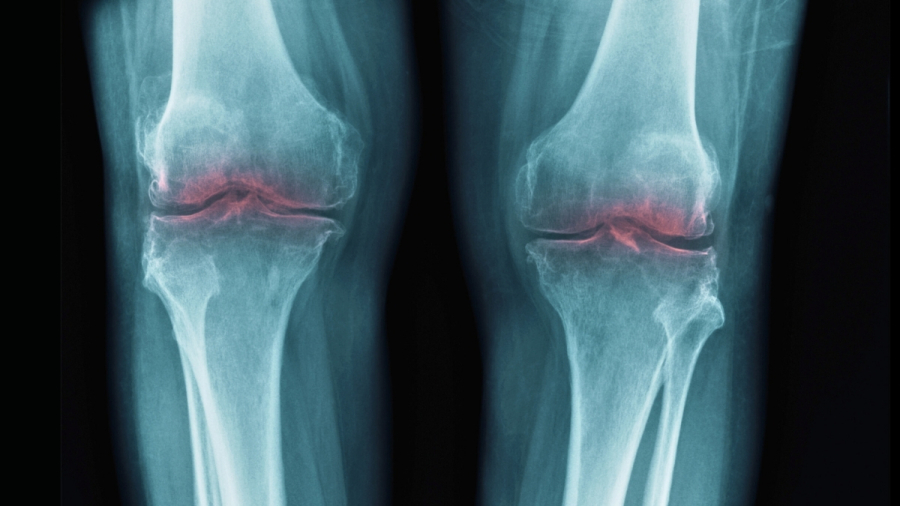

Μια μελέτη σε ποντίκια από ερευνητές του Πανεπιστημίου του Στάνφορντ ανίχνευσε την απώλεια χόνδρου που συνοδεύει τη γήρανση σε μία μόνο πρωτεΐνη, υποδεικνύοντας θεραπείες που μπορεί κάποια μέρα να αποκαταστήσουν την κινητικότητα και να μειώσουν την ενόχληση στους ηλικιωμένους, συμβάλλοντας με αυτόν τον τρόπο στην αντιμετώπιση της οστεοαρθρίτιδας.

Αυτό οδήγησε τους επιστήμονες να εξετάσουν εάν η 15-PGDH μπορεί να εμπλέκεται στην οστεοαρθρίτιδα, όπου η καταπόνηση στις αρθρώσεις οδηγεί στη διάσπαση του κολλαγόνου στον χόνδρο, προκαλώντας φλεγμονή και πόνο.

Το ίδιο πείραμα δοκιμάστηκε επίσης σε δείγματα ανθρώπινου ιστού που ελήφθησαν από άτομα που είχαν υποβληθεί σε χειρουργική επέμβαση αντικατάστασης γόνατος. Και πάλι, υπήρχαν σαφή σημάδια αναγέννησης, με τον χόνδρο να γίνεται πιο άκαμπτος και να δείχνει λιγότερα σημάδια φλεγμονής.

Εκτός από την αντικατάσταση των αρθρώσεων που επηρεάζονται, οι τρέχουσες επιλογές θεραπείας για την οστεοαρθρίτιδα περιορίζονται στη διαχείριση του πόνου. Παρά την πολλά υποσχόμενη έρευνα τα τελευταία χρόνια, δεν έχουμε ακόμη τίποτα που να αντιμετωπίζει την αιτία της πάθησης.